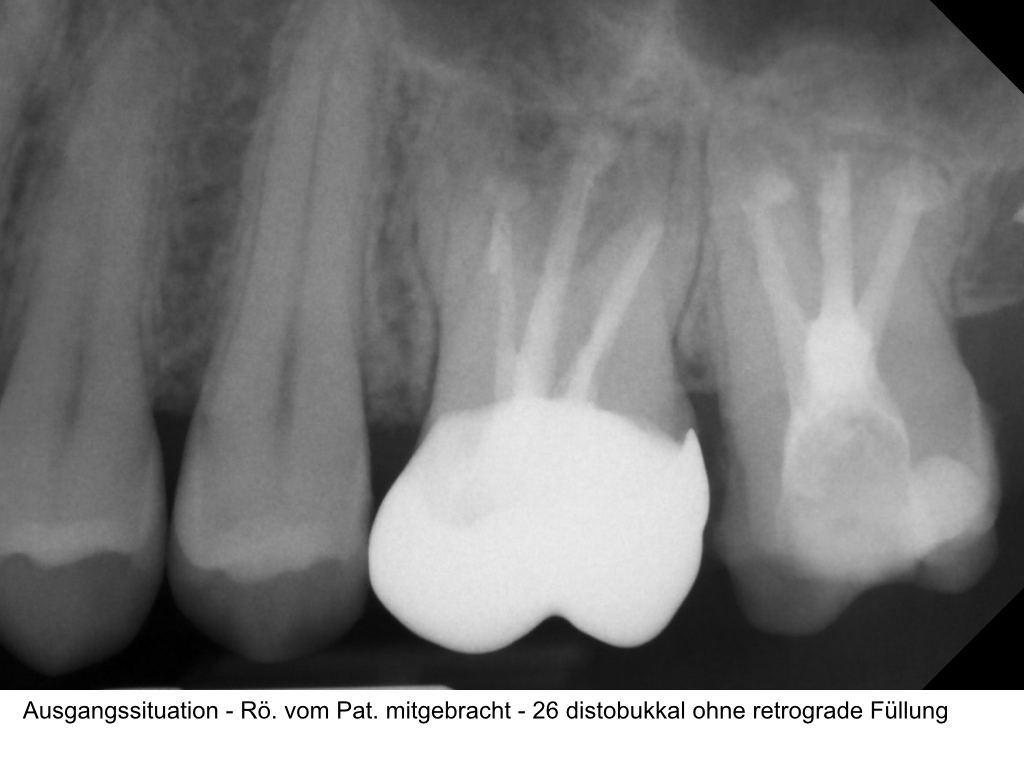

Zustand nach WSR